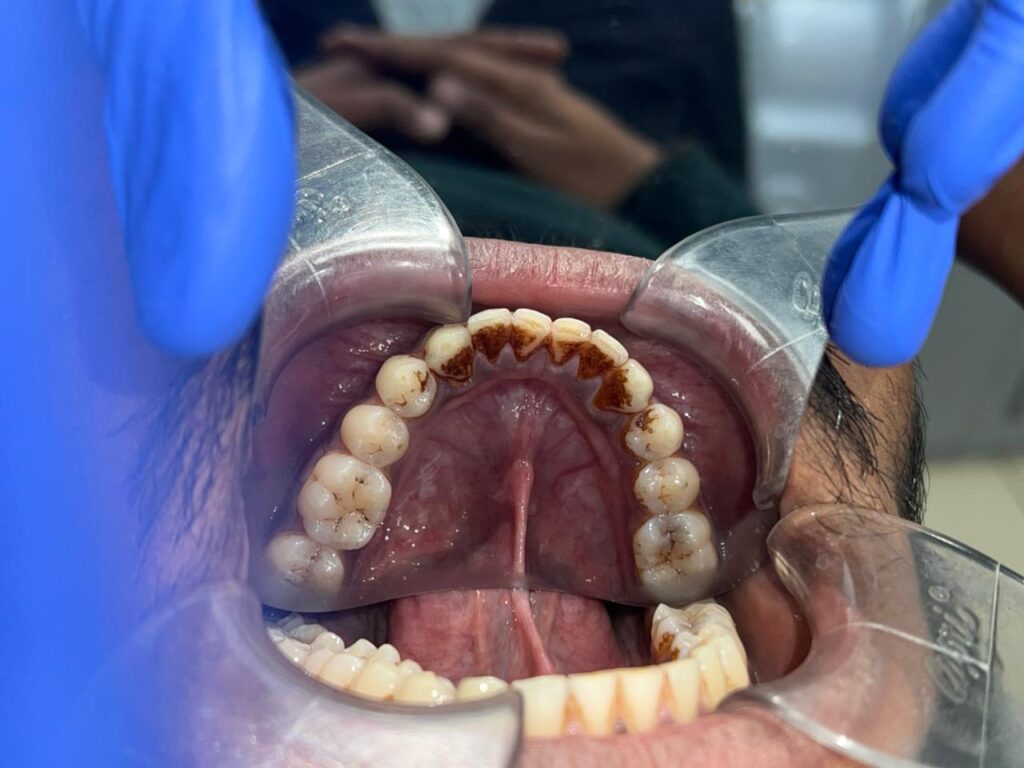

Step 1: Scaling (Deep Cleaning)

Scaling removes:

- Tartar (calculus)

- Plaque

- Surface stains

- Bacterial deposits

- Yellow/brown layers on teeth

This alone can significantly improve tooth color and oral hygiene.